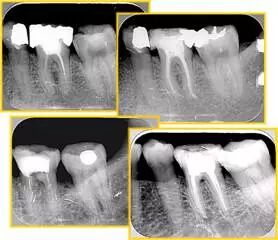

往期精彩图集

牙胶尖什么颜色【根管治疗】根管治疗的细节把握_https://www.jmylbn.com_新闻资讯_第38张

牙胶尖什么颜色【根管治疗】根管治疗的细节把握_https://www.jmylbn.com_新闻资讯_第39张

牙胶尖什么颜色【根管治疗】根管治疗的细节把握_https://www.jmylbn.com_新闻资讯_第40张

牙胶尖什么颜色【根管治疗】根管治疗的细节把握_https://www.jmylbn.com_新闻资讯_第41张

牙胶尖什么颜色【根管治疗】根管治疗的细节把握_https://www.jmylbn.com_新闻资讯_第42张

牙胶尖什么颜色【根管治疗】根管治疗的细节把握_https://www.jmylbn.com_新闻资讯_第43张

牙胶尖什么颜色【根管治疗】根管治疗的细节把握_https://www.jmylbn.com_新闻资讯_第44张

牙胶尖什么颜色【根管治疗】根管治疗的细节把握_https://www.jmylbn.com_新闻资讯_第45张

牙胶尖什么颜色【根管治疗】根管治疗的细节把握_https://www.jmylbn.com_新闻资讯_第46张

牙胶尖什么颜色【根管治疗】根管治疗的细节把握_https://www.jmylbn.com_新闻资讯_第47张

牙胶尖什么颜色【根管治疗】根管治疗的细节把握_https://www.jmylbn.com_新闻资讯_第48张

牙胶尖什么颜色【根管治疗】根管治疗的细节把握_https://www.jmylbn.com_新闻资讯_第49张

牙胶尖什么颜色【根管治疗】根管治疗的细节把握_https://www.jmylbn.com_新闻资讯_第50张